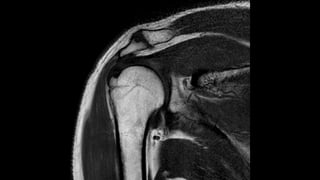

O documento aborda lesões no ombro, dividindo-as por faixas etárias: fraturas de clavícula em crianças, luxações em adultos e fraturas do úmero proximal em idosos. Descreve também técnicas de avaliação radiográfica e suas variações, incluindo incidências específicas para diagnóstico. Além disso, são mencionados métodos de imagem alternativos para a avaliação de partes moles e condições articulares.